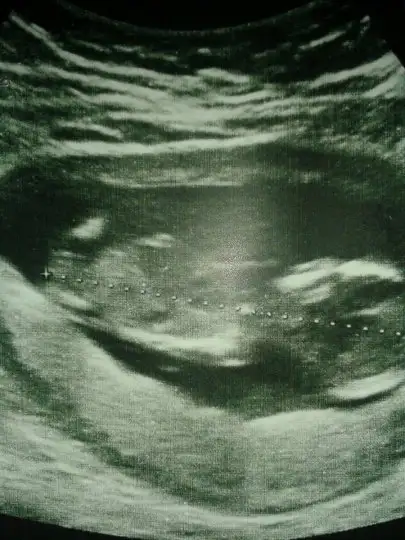

Aslında daha önce sormuştum ama tek bir arkadaş yorum yazdı belki farklı görüşler olur diye tekrar fikir almak istedim :) burda 12+1 iz normalde ama 3 gün önden gidiyoruz 12+4 görünüyor o yüzden minnağım :)

kiz cnm bnm ole gorunuo nub

Kiz canım öyle gozukuyorKIZLAR SİZCE BENİMKİ NE